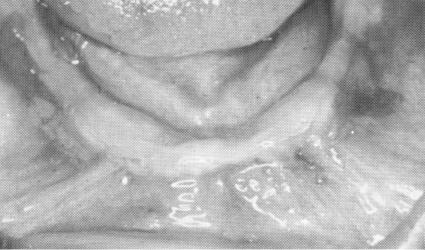

Fig. 11-136. The edentulous mandible.

Restoring an edentulous jaw with endosseous implants, even prior to the evolution of the blade variety, has been more successful in the mandible than in the maxilla. Mandibular bone is much denser and the thick cortical plate along the alveolar crest

provides an ideal brace for the shoulders of the blade. The law of gravity also favors lower implant cases as compared with upper ones.